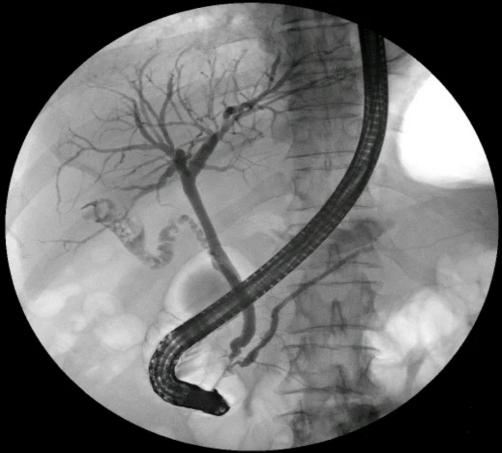

ERCP,即经内镜逆行胰胆管造影,是将带摄像机的十二指肠镜经口腔、食道送入十二指肠,再通过十二指肠乳头向胆管或胰管注入造影剂,借助X线摄片清晰显示胰胆管系统,同时完成诊断与治疗的技术。

• 通过造影清晰呈现胆管、胰腺导管的解剖结构与病变位置,让“看不见的病灶”变“清晰可见”;